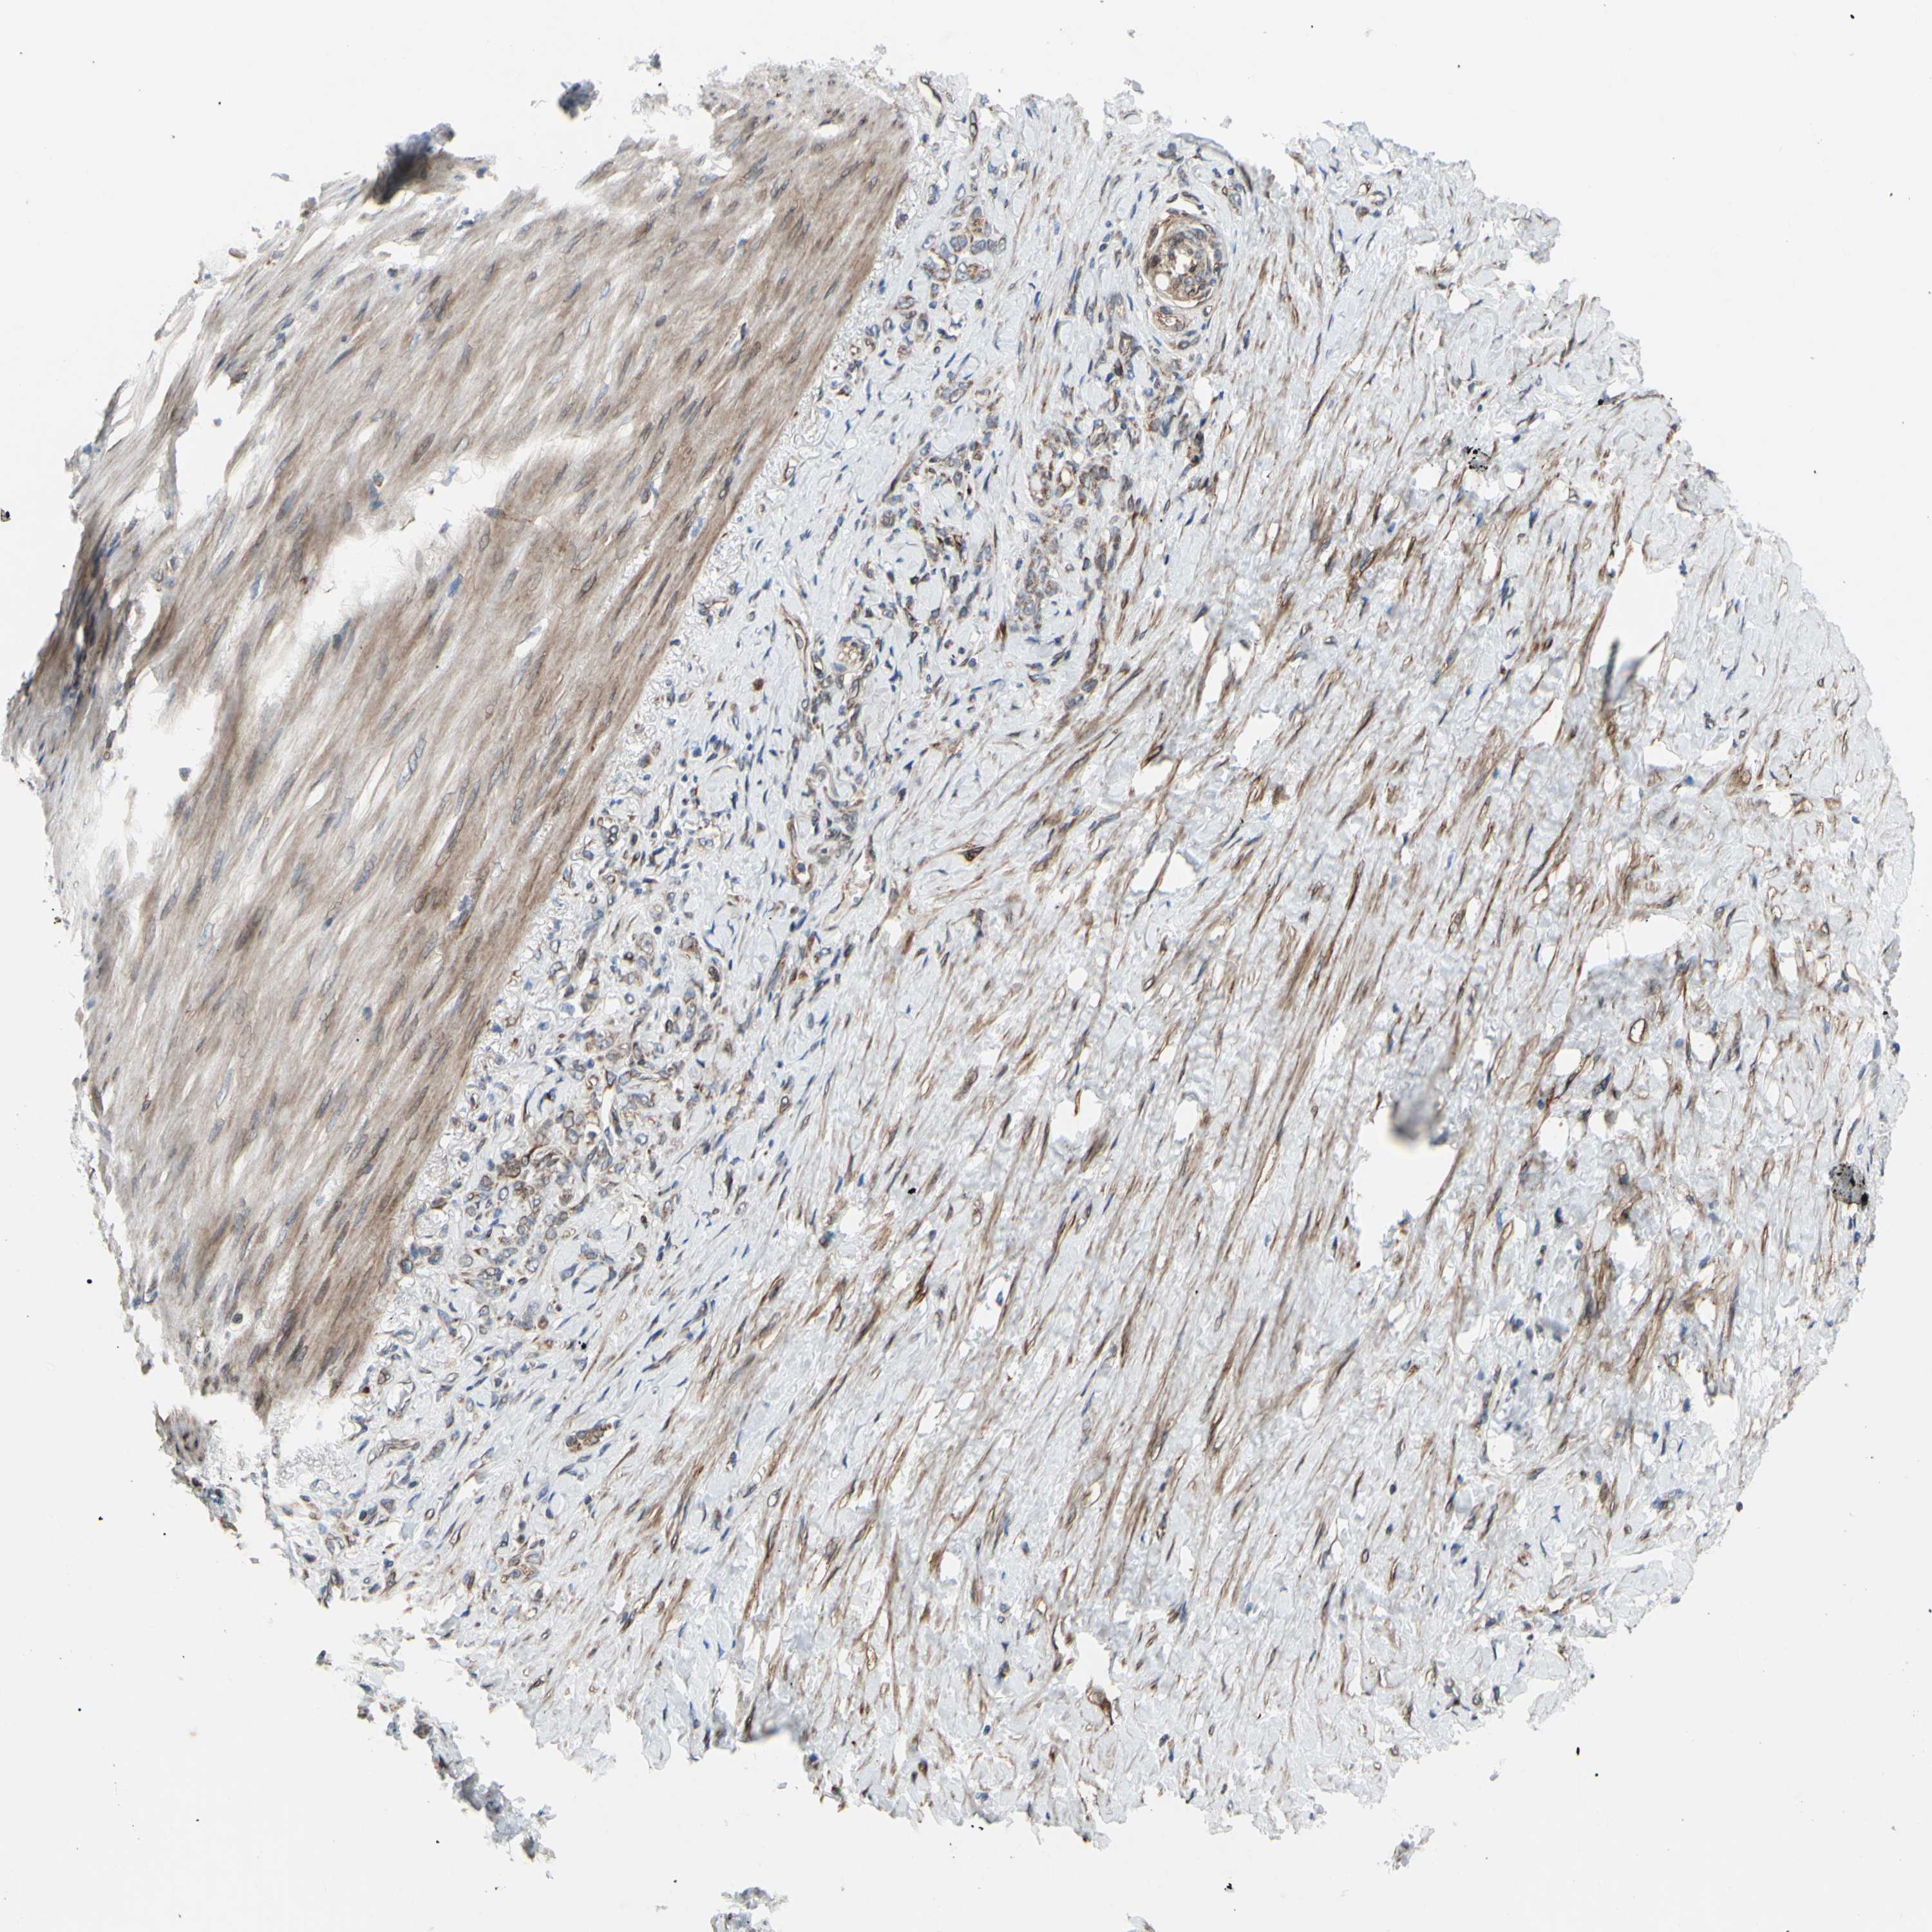

STOMACH CANCER - Protein expressioni

A mouse-over function shows sample information and annotation data. Click on an image to view it in a full screen mode. Samples can be filtered based on level of antibody staining by selecting one or several of the following categories: high, medium, low and not detected. The assay and annotation is described here.

Antibody stainingi

Antibody staining in the annotated cell types in the current human tissue is reported as not detected, low, medium, or high, based on conventional immunohistochemistry profiling in selected tissues. This score is based on the combination of the staining intensity and fraction of stained cells.

Each image is clickable and will lead to virtual microscopy that enables deeper exploration of all samples and also displays staining intensity scores, fraction scores and subcellular localization as well as patient and tissue information for each sample.

Antibody HPA002859

Antibody CAB011655

Staining

High

Medium

Low

Not detected

Intensity

Strong

Moderate

Weak

Negative

Quantity

>75%

75%-25%

<25%

None

Location

Nuclear

Cytoplasmic/membranous

Cytoplasmic/membranous,nuclear

Adenocarcinoma, NOS

Adenocarcinoma, High grade